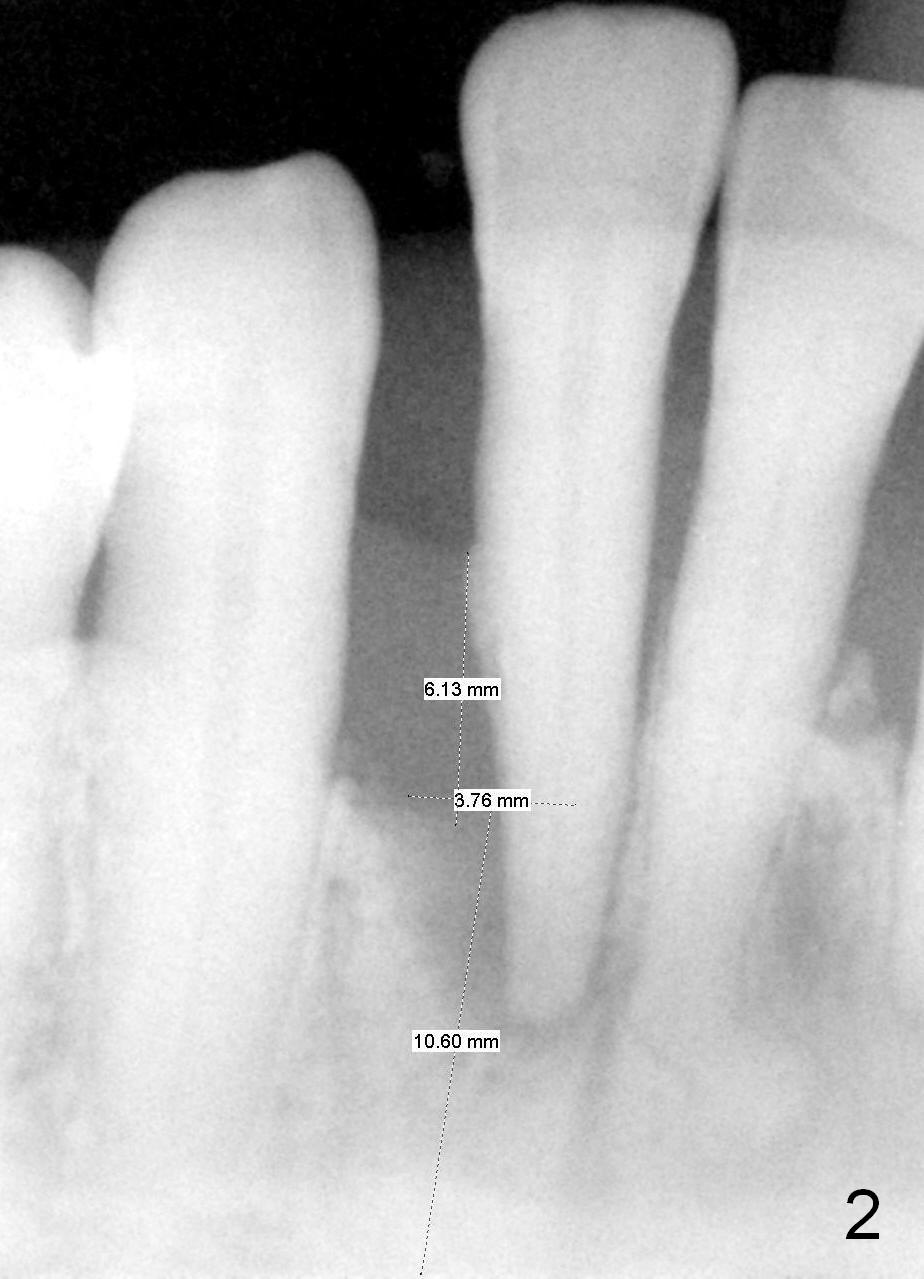

A tentative design is as follows: a bone-level implant is placed 4 mm subgingival (Fig.3, total gingival height 6 mm (Fig.2)). The cuff will be 4 mm. The most coronal threads are covered by bone graft (red circles).

If the patient turns out to be small in statue, crest width is narrow (by using bone caliper), and/or pilot drills are placed too buccal or lingual, a smaller 1 piece implant is to be chosen (2.5 mm). The lower incisor is the smallest tooth in the mouth. The small implant should sustain mastication.